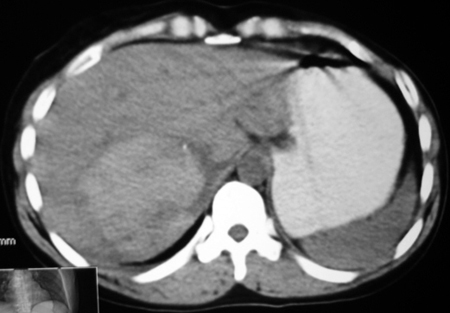

以下是引用bmw011在2009-4-23 13:28:00的发言:[br]考虑右肾包膜下血肿。

以下是引用卜一在2009-4-23 15:43:00的发言:[br]考虑右肾包膜下血肿,不排除占位病变伴出血可能,建议进一步检查。